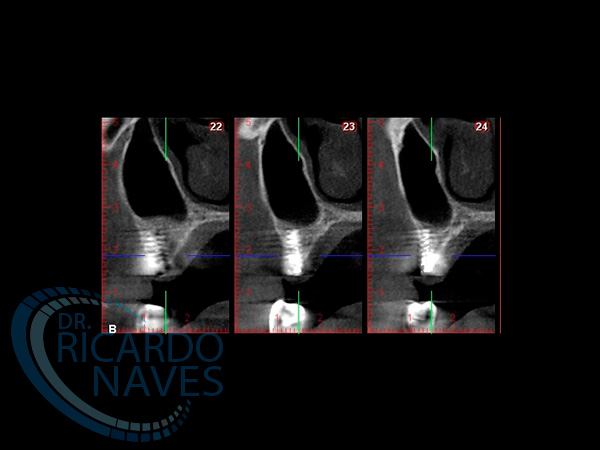

Elevación de seno maxilar con aloinjerto e instalación inmediata de implantes.Control a los 15 días post cirugía.VOLVER Comparte esta historia, elija su plataforma! FacebookXLinkedInPinterestCorreo electrónico